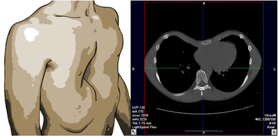

누두흉(funnel chest)이란 앞 흉벽(가슴)이 선천적으로 과도하게 함몰된 기형을 말하는 것으로서 함몰흉, 오목가슴이라고도 합니다. 흉골의 선천성 기형 중 가장 흔한 병으로 300-400명당 1명꼴로 발생합니다. 보통 출생 직후부터 나타나며 나이가 들면서 점점 진행하는 것이 보통입니다.

최근에는 양쪽 옆가슴에 약 2cm 정도의 피부절개 후 적당한 모양의 구부러진 쇠막대를 앞가슴 밑으로 삽입하여 함몰된 앞가슴을 들어 올려 원하는 모양으로 가슴을 복원시켜주고 가슴뼈가 안정되는 2년 후에 쇠막대를 제거하는 너스 수술법을 많이 시행하고 있습니다.